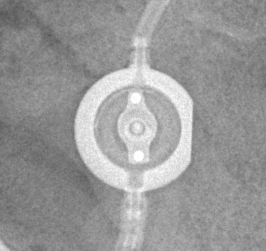

Programmable Valves

Medtronic Strata NSC

Medtronic Strata NSC valves are adjustable csf shunt valves.